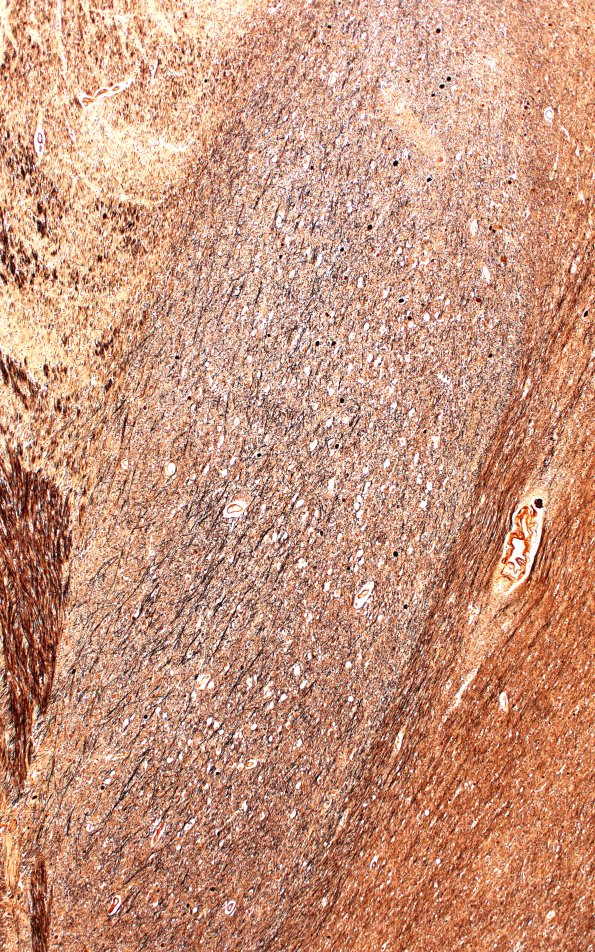

Washington University Experience | NEURODEGENERATION | Progressive Supranuclear Palsy (PSP) | 18B3 (Case 18) Biels Subthal 4XA

Higher magnification images of the subthalamic neurons showing numerous globose tangles (Bielschowsky)